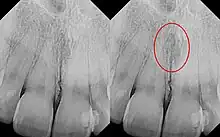

Identical images with heart-shaped radiolucency highlighted in right film.

The nasopalatine duct cyst (NPDC) occurs in the median of the palate, usually anterior to first molars. It often appears between the roots of the maxillary central incisors. Radiographically, it may often appear as a heart-shaped radiolucency. It is usually asymptomatic, but may sometimes produce an elevation in the anterior portion of the palate. It was first described by Meyer in 1914.[1]

As a cyst, the nasopalatine duct cyst requires histological analysis for a definitive diagnosis. Radiographically, the nasopalatine cyst appears as a well-demarcated round, ovoid, or heart-shaped structure presenting in the midline of the maxilla.[6]